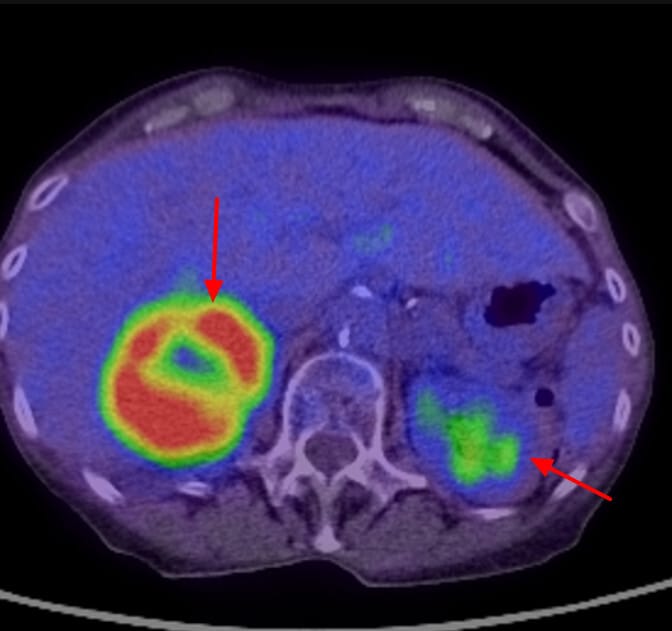

PET-CT 소견

원발 종양과 전신 전이 병소를 동시에 확인할 수 있어 병기 결정에 중요합니다.

| 고대사 활성을 보이는 종괴 |

| 폐의 중심부 종괴에서 FDG 섭취 증가 (SUV↑) |

| 다발성 원격 전이 병소 |

| 간, 부신, 뼈 등 다양한 장기로 퍼진 고섭취 병변이 관찰됨 |

영상 소견상 특징

- Large right adrenal metastasis

- Marked FDG uptake